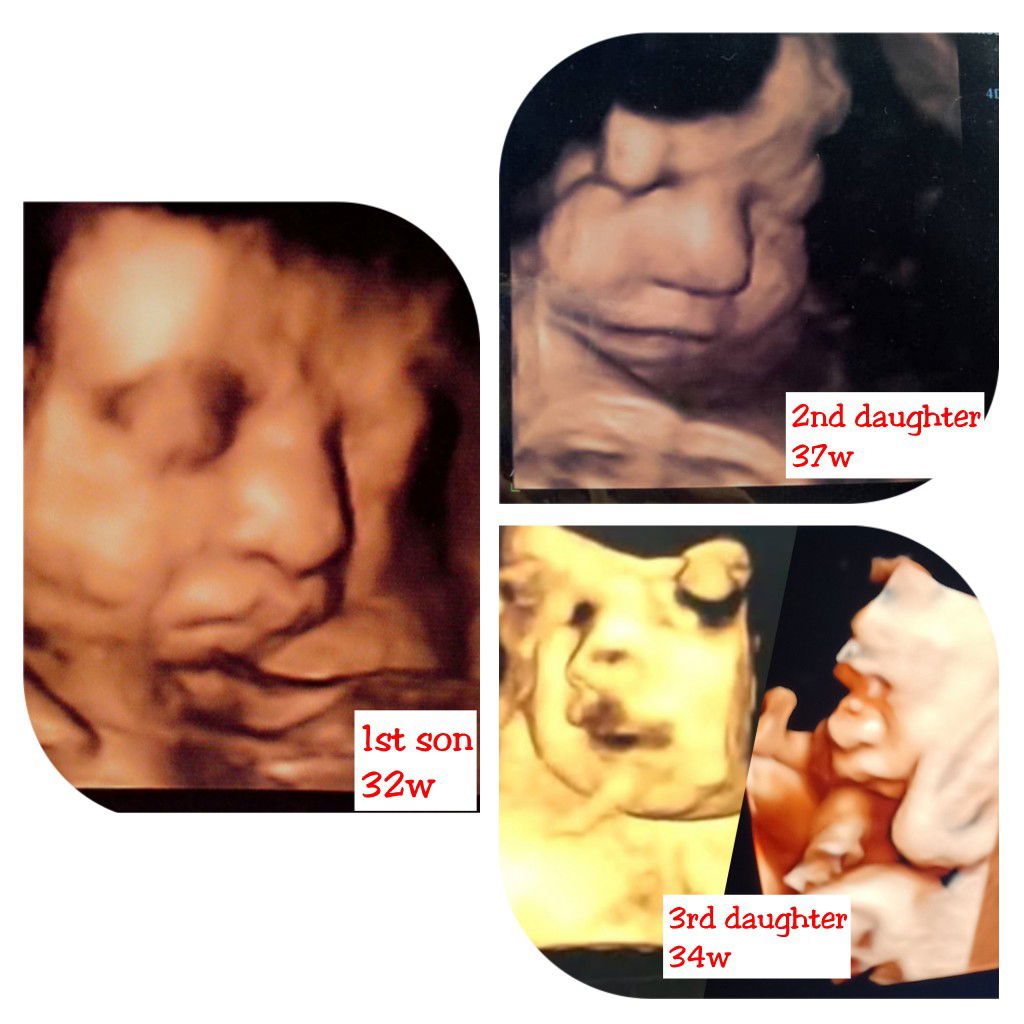

mommy of 3 childrens